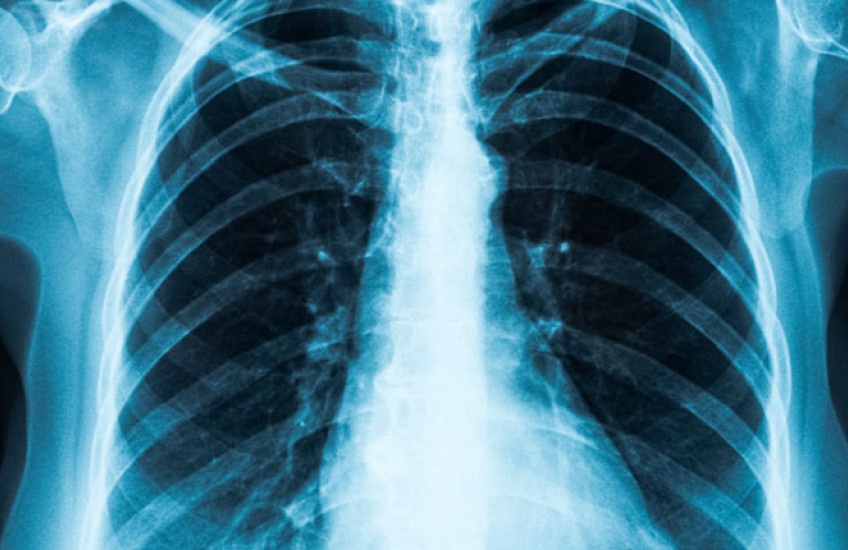

Harvard Medical School scientists and colleagues at Stanford University have developed an artificial intelligence diagnostic tool that can detect diseases on chest X-rays directly from natural-language descriptions contained in accompanying clinical reports.

A report on the work, published Sept. 15 in Nature Biomedical Engineering, shows that the model, called CheXzero, performed on par with human radiologists in its ability to detect pathologies on chest X-rays.